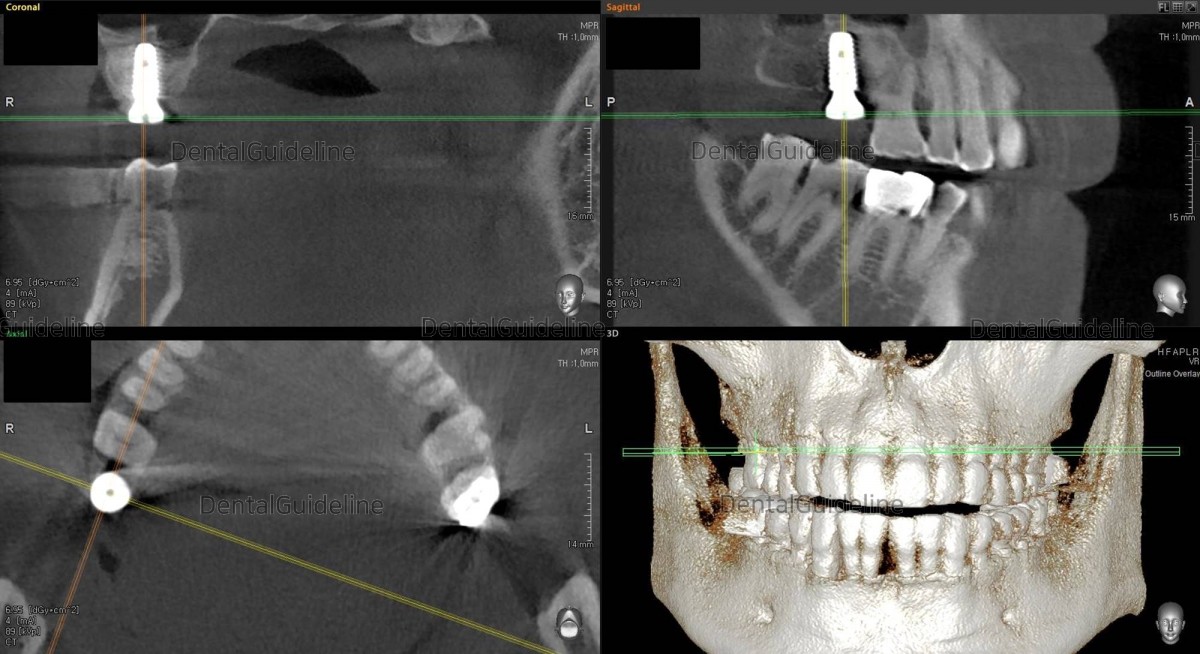

The implant was placed with the size of 5*10 Hiossen(=Osstem) TS. And HA was connected on-site at the same time.

CBCT